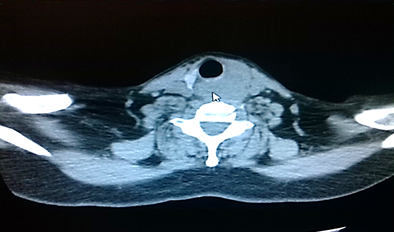

Pruebas de laboratorio: se aprecia leucocitosis en 12.000cel/mm3 y luego progresa a 24.500cel/mm3, polimorfo nuclear 90%, valores de glucosa en sangre elevada. Se le realiza rayos x de cuello (Figura 2. Anexos), y ecosonograma de región cervical, donde se describe una lesión ocupante de espacio alrededor de la tráquea hacia el lado izquierdo, de 4x 2 cm, heterogénea de bordes bien circunscritos. No presenta vascularidad al uso del Doppler. El lóbulo izquierdo del tiroides, muestra efecto de masa en su cara inferior. Concluye con una lesión ocupante de espacio en región traqueal izquierda sugerente de absceso frio. Se le realiza estudio de tomografía computarizada de cuello (Figura. 3, 4, 5. Anexos), y tórax, apreciando en región lateral izquierda del cuello, hiperdensidad paralela a la tráquea y glándula tiroidea, haciendo efecto de masa compresiva sobre las estructuras cercanas.

IMG_20181019_155138

Figura 3. Tomografía axial computarizada de región cervical. apreciando en región lateral izquierda del cuello, hiperdensidad paralela a la tráquea y glándula tiroidea, haciendo efecto de masa compresiva sobre las estructuras cercanas.

Fuente: Fotografía realizada por Dra. María Pulgar.